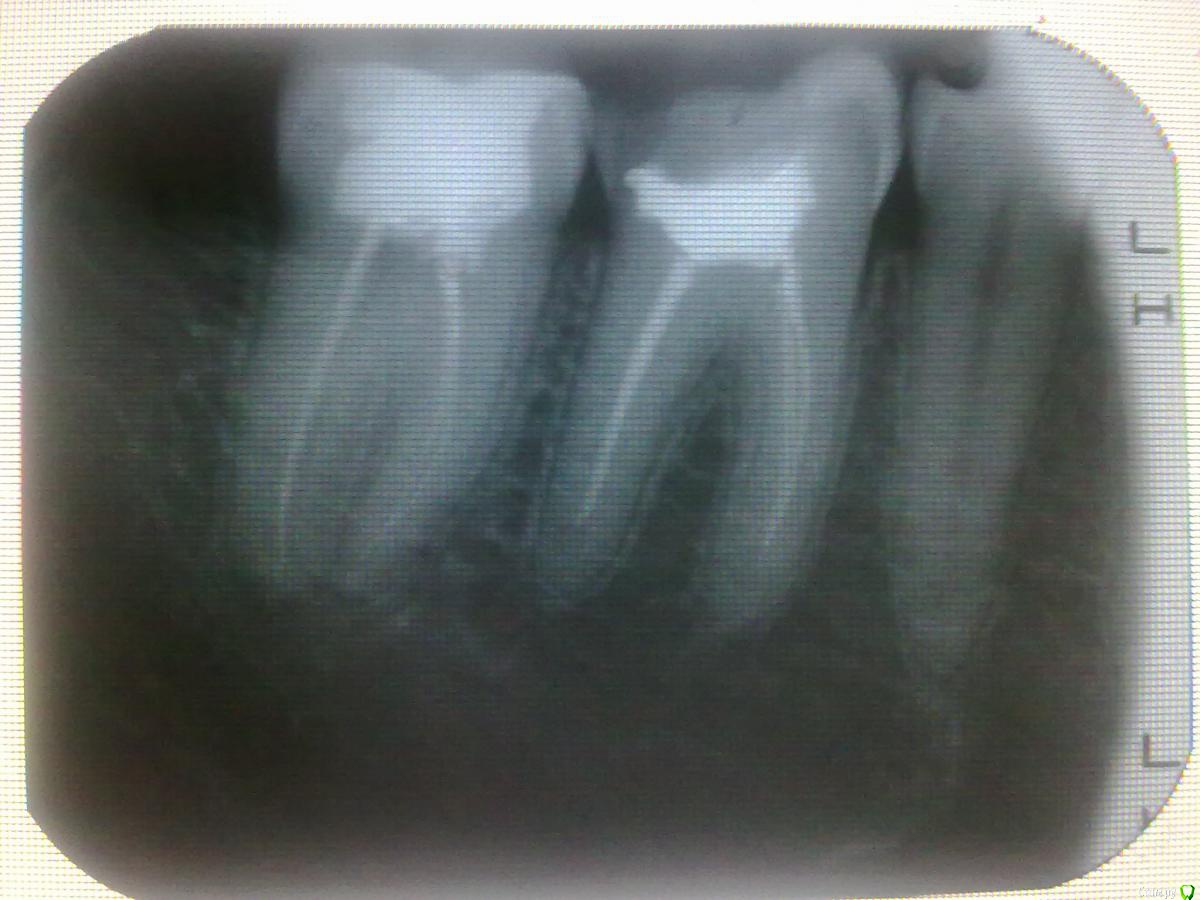

zdoroviy Опубликовано 4 апреля, 2017 Поделиться Опубликовано 4 апреля, 2017 Добрый день, болит десна возле нижнего 6 зуба слева, в зубе нет нервов, пломба стоит, но старая. Подскажите в чем причина может быть? стоит ли перепломбировать зуб или каналы? Можно его сохранить и не удалять? Ссылка на комментарий

Карен Аванесов Опубликовано 4 апреля, 2017 Поделиться Опубликовано 4 апреля, 2017 Зуб сгнивает под старой пломбой, пора делать коронку. Ссылка на комментарий